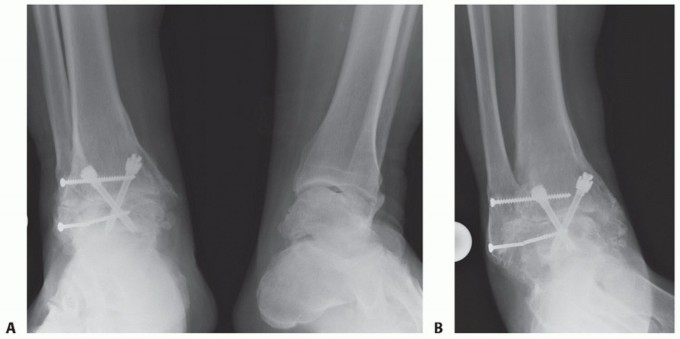

DEFINITION Osteochondral lesions of the talus (OLT) are common conditions that can involve both the cartilage…

DEFINITION The term osteochondral lesion of the talus (OLT) refers to any pathology of the talar articular ca…